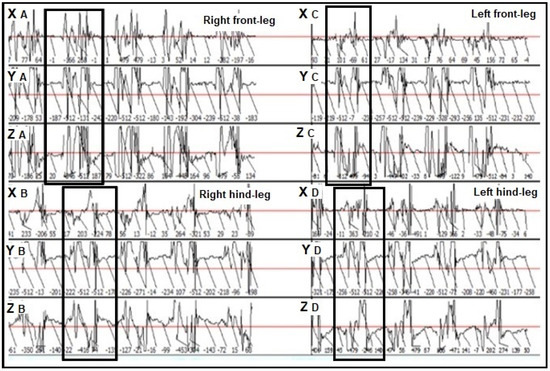

3.1. Descriptive Statistics for the Mean Impulse Numbers Recorded in the Lame and Sound Contralateral Legs of the Assessed Horses